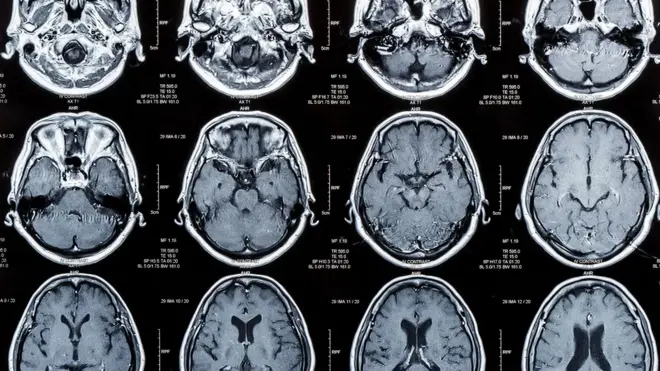

ඩිමෙන්ෂියා රෝගය යනු කුමක් ද?

ඩිමෙන්ෂියා යනු විවිධ හේතු නිසා මොළයේ සෛල විනාශ වීමෙන් ඇති වන රෝගී තත්ත්වයක් බව ජාතික මානසික සෞඛ්ය විද්යායතනයේ ජ්යෙෂ්ඨ විශේෂඥ මනෝ වෛද්ය කපිල රණසිංහ බීබීසී සිංහල සේවයට පැවසීය.

“ඩිමෙන්ෂියා කියන්නේ මතකය, කල්පනාව, බුද්ධිය අඩු වෙලා තමන්ගේ එදිනෙදා ක්රියාකාරීත්වය අඩපණ වෙලා යන රෝග තත්ත්වයන් ගණනාවකට කියන පොදු නම. ඩිමෙන්ෂියා වර්ග ගණනාවක් තියෙනවා. ඒකෙන් ලෝකයේ බහුලව ම තියෙන්නෙ ඇල්සයිමර් කියන තත්ත්වය. ඊට පස්සේ වැස්ක්යුලර් ඩිමෙන්ෂියා හෙවත් රුධිර නාල අඩපණ වීමෙන් ඇති වන රෝග තත්ත්වයක් දෙවෙනියට තියෙනවා. ඒ වගේ විවිධ හේතු නිසා මොළයේ සෛලවලට සිදුවෙන හානිවලින් තමයි මේ රෝගී තත්ත්වය ඇති වෙන්නේ.”

- ඩිමෙන්ෂියා රෝගය ඇති වන්නේ විවිධ රෝග සහ අනතුරු නිසා මොළයට හානි සිදුවීමෙනි. ලෝකයේ වඩාත් පොදු ඩිමෙන්ෂියා තත්ත්වය ඇල්සයිමර් රෝගී තත්ත්වය වන අතර, ඩිමෙන්ෂියා රෝගීන්ගෙන් 60-70%ක් එම තත්ත්වයේ පවතී.